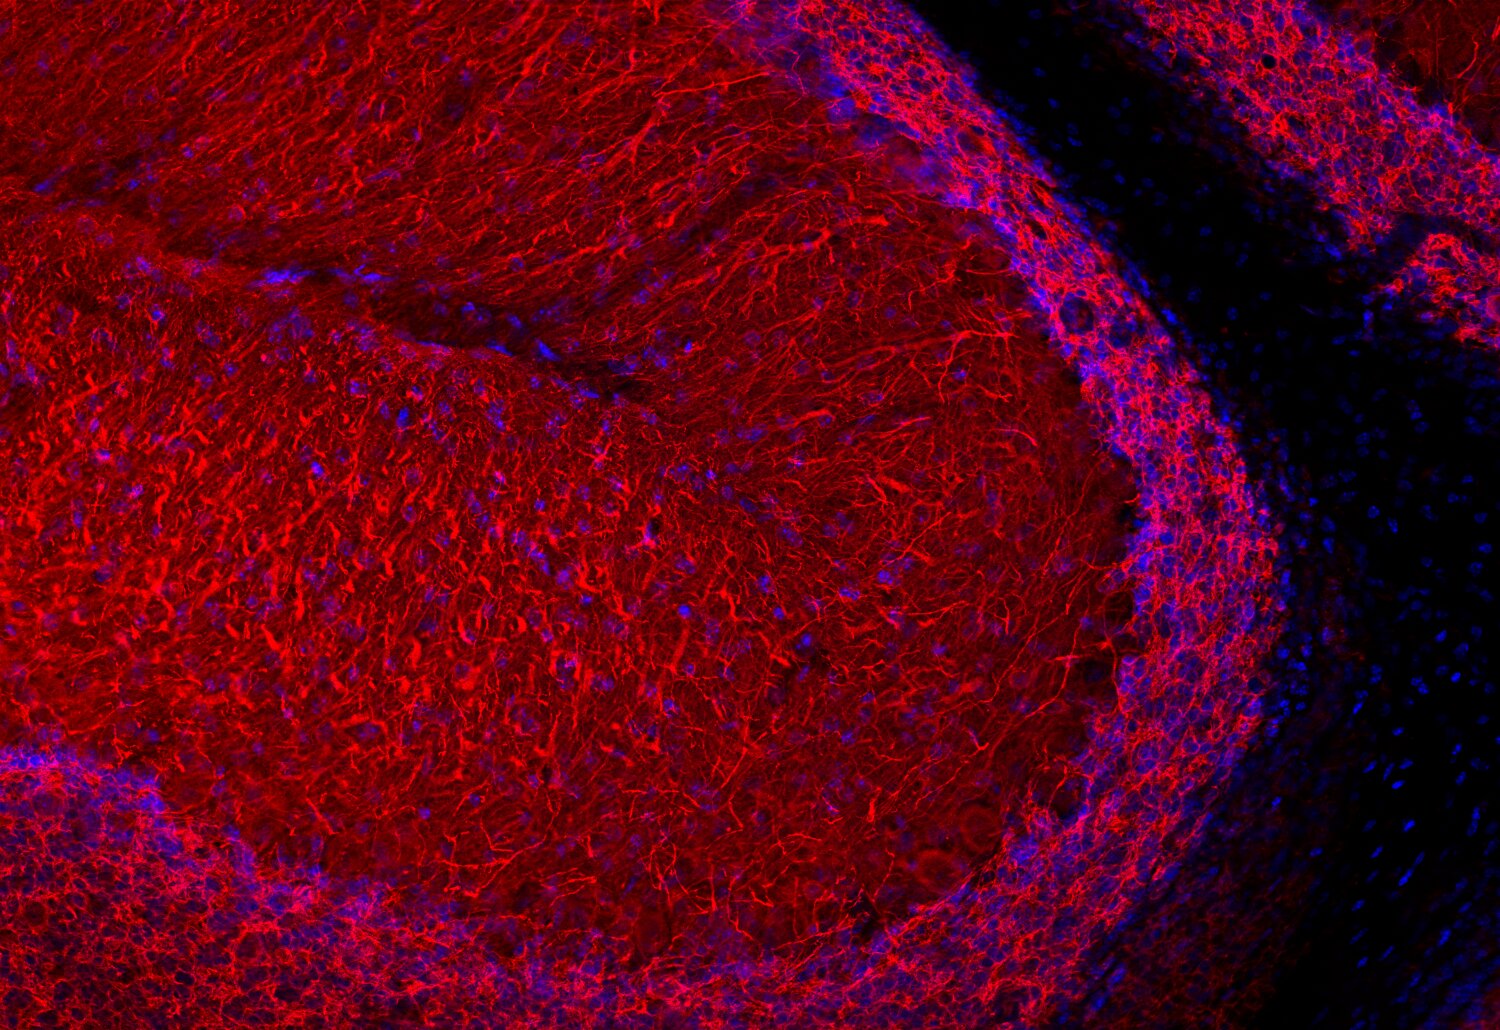

RNA Assay Reagent Kit | Revvity。Recombinant Human Lymphotoxin alpha1/beta2 Protein 678-LY。Synaptic Systems - MAP2。一度だけ着用しました。ホームクリーニング後畳んでしまってありました。即完売した商品です。身幅72肩幅64着丈77そで丈25ご理解のある方のみご購入よろしくお願い致します。お値下げの時は、値下げ依頼にて希望価格を記入してください。。ZIP8/SLC39A8 (E3V8K) Rabbit mAb | Cell Signaling Technology。。maison special ボリュームウエストパーツウェア。LEPSIM♡ギャザーWZIPベスト。etsinta エシンタ リメイクチルデンベスト ロング チャオパニック